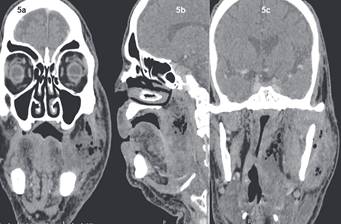

Caso N°2: Paciente sexo masculino 71 años con Diabetes Mellitus tipo II insulino requiriente, refiere que sufrió un traumatismo con elemento contundente en región geniana izquierda de un mes de evolución, posterior al golpe cursa con dolor y aumento de volumen en región mandibular izquierda con disfagia y dislalia. Consulta en múltiples servicios de urgencia, siendo tratado con Amoxicilina con Ácido Clavulánico y Analgésicos no esteroidales (Aines), sin una respuesta favorable. Evoluciona con incremento del dolor y aumento de volumen. Posteriormente cursa con fiebre y compromiso del estado general y 6 días después consulta al servicio de urgencia del hospital. Al ingreso en el servicio de urgencias, se presenta normotenso y afebril con dolor preauricular punzante progresivo. Al examen físico presenta luxación mandibular izquierda con imposibilidad de cerrar la boca, y desviación severa de la mandíbula a la izquierda asociado a un aumento de volumen parotídeo izquierdo presentando una PCR de 290mg/dl (fig. 3). Al día siguiente es evaluado por Cirugía Maxilofacial, donde se presenta febril, confuso, desorientado y con otorrea izquierda. La evaluación por el servicio de Otorrinolaringología constata presencia de exposición ósea y secreción purulenta en oído izquierdo. Se hospitaliza y se inicia antibioterapia empírica con Ceftriaxona y Metronidazol endovenosa, a su vez se realizaron hemocultivos y cultivo de secreción del conducto auditivo externo (CAE) izquierdo, siendo estos negativos. La TC evidencia fractura de pared anterior del CAE, luxación de articulación témporo-mandibular (ATM) izquierda y con un proceso inflamatorio extenso en el espacio masticatorio izquierdo (Fig.4). Evoluciona desfavorablemente, con disfagia, requerimientos de oxigenoterapia, aumento de volumen facial y cervical progresivo, elevación de parámetros inflamatorios y coagulopatía. Se modificó la terapia antibiótica a Sulbamox y se tomó una TC con contraste que muestra un aumento de volumen cervical difuso de espacio masticatorio, parafaringeo y bucofaríngeo con abundantes burbujas de aire (Fig.5). Al día siguiente se realizó aseo quirúrgico en pabellón de urgencia de espacios cervicales profundos; intubado con traqueotomía, mediante acceso preauricular, se realizó la exploración de ATM izquierda con extensión cervical e instalación de drenajes. Se realizaron cultivos de las cavidades abscedadas. Posterior al pabellón ingresó a la unidad de cuidados intensivos (UCI), sedado con asistencia ventilatoria mecánica y se continuó el manejo del shock séptico, con apoyo de drogas vasoactivas por al menos 48hrs. Evolucionó con fascitis necrotizante en región cervical anterior y posterior izquierda, sin avanzar a mediastinitis; además de una hipertensión arterial concomitante. Se realizaron otros 3 aseos quirúrgicos en pabellón y nuevos cultivos microbiológicos. Luego de 12 días en la UCI regresa a sala donde presenta una mejoría sostenida y progresiva. Los cultivos mostraron Staphilococus Epidermidis, Cándida y bacilos Gram +, que fueron tratados con antibioterapia endovenosa (Vancomicina, Sulbamox y Fluconazol) hasta completar 6 semanas siendo dado de Alta a los 2 meses desde el ingreso sin signos de infección y parámetro inflamatorios normales (Fig. 6). Durante este tiempo fue evaluado y tratado por los equipos de cirugía maxilofacial, otorrinolaringología, infectología, medicina y fonoaudilogía.